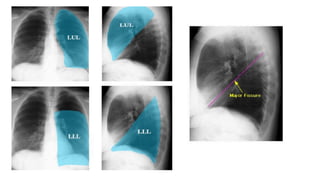

Left upper lobe consolidation

loss of left heart border consistent with

left lingula consolidation.

Left upper lobe airspace consolidation with

air bronchograms

Left lower lobe consolidation

● Density in left lower lung field, left heart silhouette intact, loss of diaphragmatic silhouette, no shift of

mediastinum, air bronchogram.